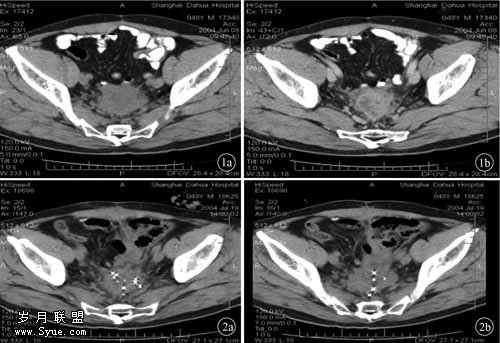

本组患者采用经尾骶部或经腹进入,部分切除盆腔复发肿块+输尿管移植+125I粒子植入方法,共治疗直肠癌根治手术后盆腔局部复发12例。无一例发生意外,除2例输尿管移植病人术后出现少量血尿并轻微尿路刺激症状,对症处理后很快消失。临床症状均出现不同程度地缓解及消失,B超显示输尿管扩张及肾盂积水明显改善,CT示盆腔肿块显著缩小(见图1、2)。不同治疗方法病人在盆腔肿块体积缩小方面进行比较(表2),并分析如下。

图1 CT示直肠癌术后盆腔转移

图2 部分切除盆腔复发肿块+125I粒子植入后